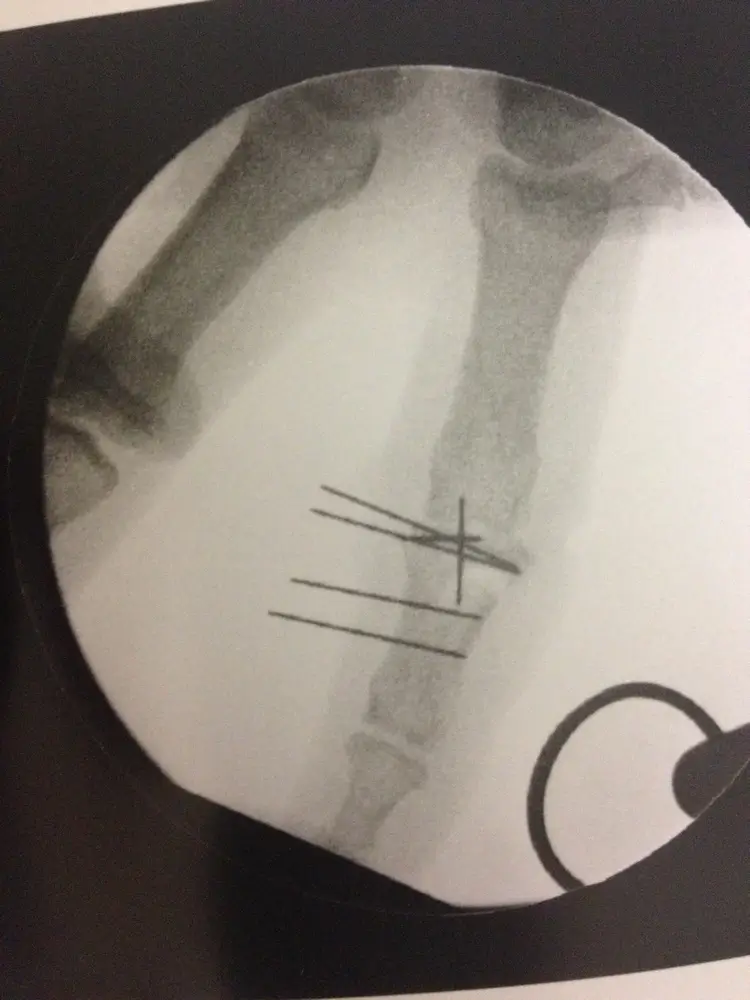

- fractures